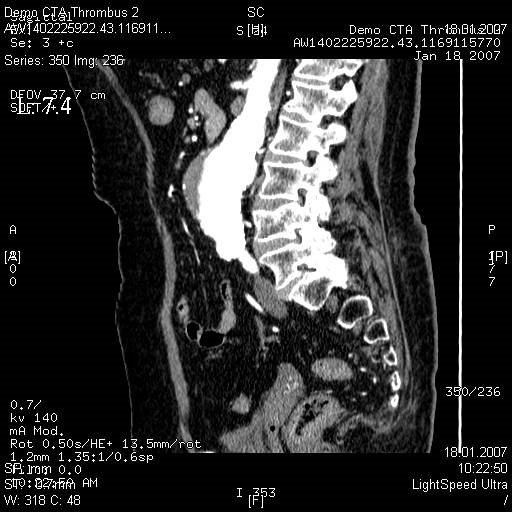

МСКТ высоко чувствительна в диагностике атеросклеротических кальцинированных, ,,мягких,, бляшек. В большинстве клиник метод МСКТ стал основным методом диагностики заболеваний сосудов сонных артерий, грудной, бюшной аорты, периферических пртерий.

- диагностика сосудистых заболеваний (аневризмы, стенозы, мальформации, аномалии развития)

- подозрение на разрыв расслоение аорты, хроническую эмболическую легочную гипертензию

Эмболии лкгочной артерии, источником которых обычно являются тромбы в венах таза и нижних конечностей являются грозным и относительно частым осложнением особенно у лежачих больных и после операции. Данные при рентгенографии неспецифичны. Без инфаркта может определяться приподнятие купола диафрагмы и сужение теней сосудов к периферии. Возможности МСКТ в диагностике ТЭЛА в ряде случаев позволяют отказаться от проведения инвазивной ангиографии.

· Подозрение на гнойно-деструктивный процесс, разрыв аорты, внутрибрюшное кровотечение, острый панкреатит, перфорация полого органа